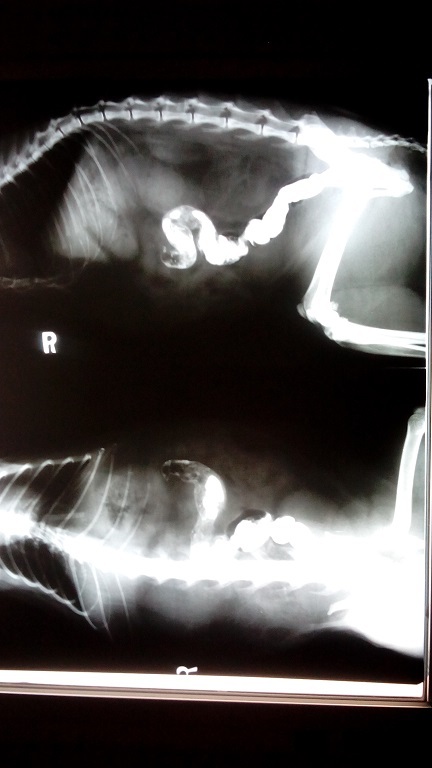

主題: 被車擦撞腳脫臼的喵 申請者姓名: 林玉真 花色: 申請日期: 2014-08-25 20:28:45 申請者部落格: 申請者臉書網址: 所在縣市/合作醫院: 新北市/成蹊動物醫院 治療費用: 5800元 需求人數: 7人 已結案 (2014-08-26 15:03:36) 報名人員: Manto Tin. x7(已付款)、 候補人員: 動物病情說明: 此貓是我長期餵養的浪貓(助紮編號04958)也是協會助罐浪貓之一,8月15日餵貓時貓咪趴在車下不動也不進食覺得有異狀立刻先補捉回家初步勘查,臉跟左後大腿有外傷應該是被車擦撞造成,送醫照X光左後腳有脫臼現象 由於貓貓已有3天不願進食所以醫院先上點滴及進行灌食 腸道內也發現有異物還好4天後有自行排出 腳脫臼的部位慢慢形成骨膜包覆(因開刀日後也不保證不會再脫臼)住院五天後食慾已有恢復 腳需要長期休養出院後由我帶回自行照顧也不會再放回原地 也感謝協會安排醫院就醫 醫療費用也請大家幫忙~感恩